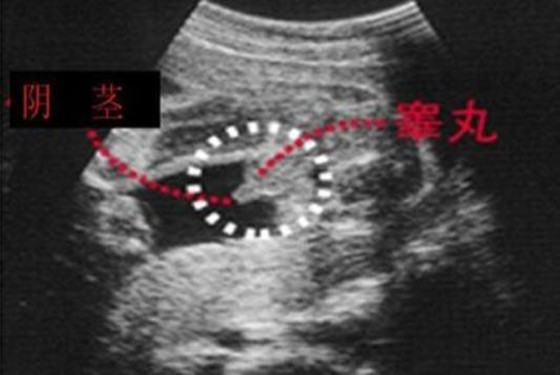

1、男宝宝的B超图:男宝宝的B超图上其实是能看到小鸡鸡的,图片的红圈处就是。这张图片上的小鸡鸡非常清晰,医生很厉害,她取的那个角度就是宝宝的屁股正下方,看的特清楚。

"凸出的东西" 是他的标记: 你们看到圆圆的是DANDAN,如果看到圆圆的加小肠的就是全部JJ

2、女宝宝的b超图:三条白线是明显的女宝特征,如果没有看到明显的三条白线,就看两腿之间有没有突出的东东,且中间有小凹槽的,就是女宝宝。